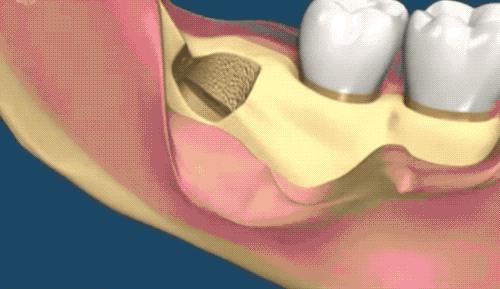

也是先切开牙肉,翻开并露出骨头,切下牙冠后取出,再处理下面的牙根。

把牙根分成两半,根据牙根的走向,分别小心地撬出来,这个过程十分考验技术,要谨慎避免损伤到下颌神经...

3.1 减少损伤 在神经束与根尖非常接近,易发生下牙槽神经损伤,此时所采用的外科技术(如牙齿劈开)必须尽量减少神经束被切断、牵拉、撕裂或者挤压,以避免神经损伤的危险。